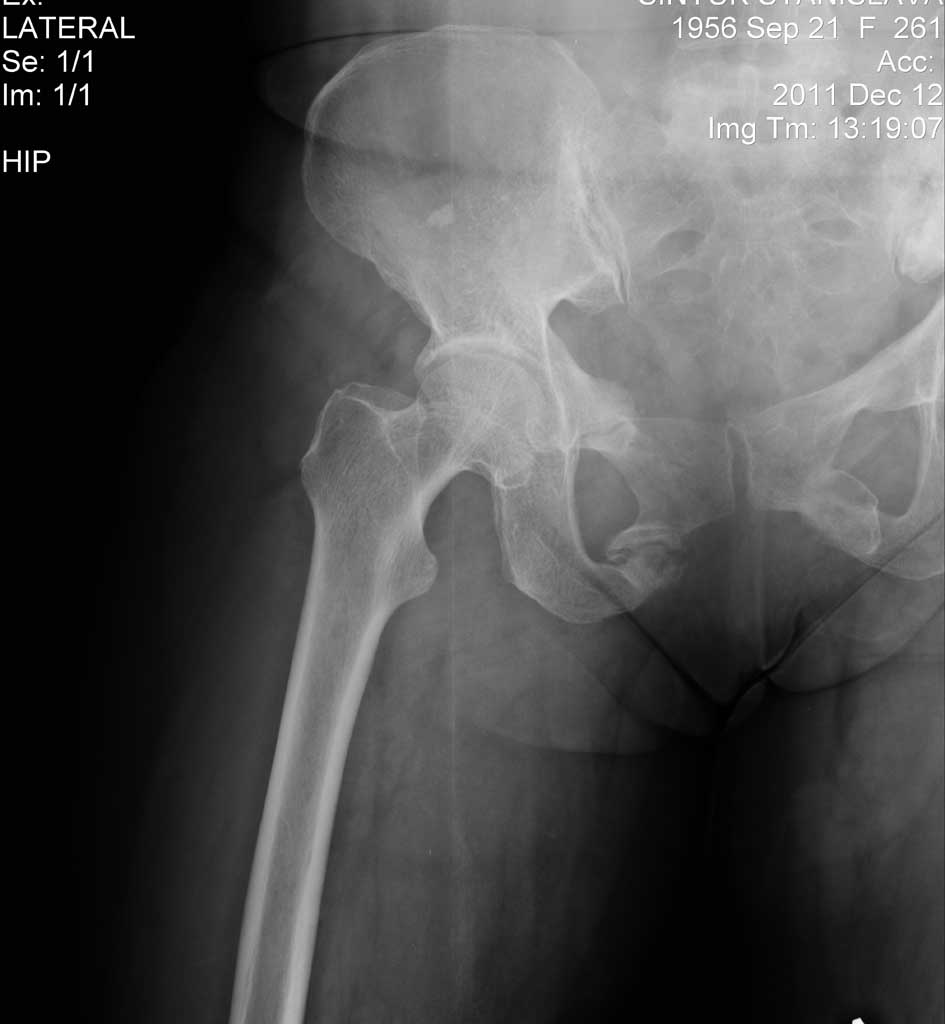

Доброго времени суток! судя по рентгенограмме у пациента ложный сустав лонной кости. Как сложатся остальные мнения не знаю но мы закрыто зафиксировали бы винтом тем самым  разрушается замыкательная пластина и склероз в зоне ложного сустава, малотравматично и низкий риск осложнения я имею ввиду нагноение раны, а еще до операции провести КТ, посмотреть задний комплекс, нередко выявляется  переломы боковой массы крестца со сдавливанием крестцового отверстия боли могут быть связаны с неврологией тогда тактика может измениться в отношении фиксации заднего комплекса. С уважением Ерсин Жунусов.

Добрый день. Есть вопрос относительно тактики лечения, синтеза(доступа, фиксатора).

Травма 3 года назад , перелом типа "бабочки".В настоящее время беспокоят боли в области

лонной кости при стоянии и ходьбе, в покое все спокойно.